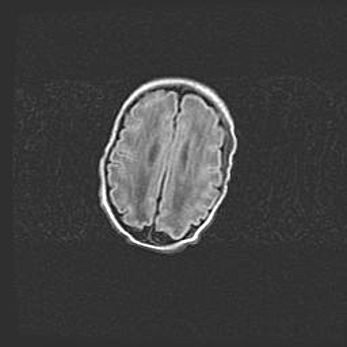

Наружная гидроцефалия с возможной атрофией височных областей.

Возраст: 28 дней

Вес: 3670 г

Пол: мужской

Окружность головы: 38 см

Срок гестации: 40 недель

Гидроцефалия головного мозга у новорожденных – это заболевание, которое характеризуется скоплением избыточного количества спинномозговой жидкости в желудочковой системе головного мозга в результате затруднения её перемещения от места выработки к месту поглощения в кровеносную систему или вследствие нарушения абсорбции. При открытой наружной форме гидроцефалии у новорожденных расширяются и переполняются субарахноидные пространства.

При нормотензивных  формах,  которые,  как  правило,  являются  следствием  перенесенных ишемических  повреждений  паренхимы  мозга,  возможно  сочетание микроцефалии  с нормотензивной гидроцефалией. В основе данных изменений лежит атрофия больших полушарий с преимущественной  локализацией  в  лобно-височных  областях.